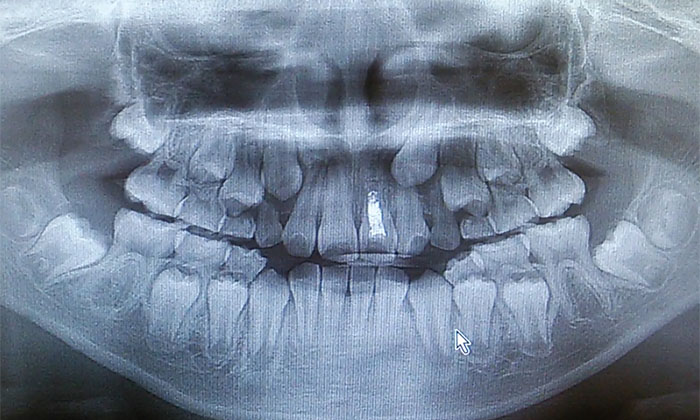

乳歯の歯の下には永久歯が生え変わる準備をしています。

1. 乳歯の下では、永久歯になるための「歯胚」ができて少しずつ成長します。

2. 永久歯の咬む部分ができて歯の根の部分ができ始めると乳歯を少しずつ吸収していきます。

3. 乳歯の根の部分が無くなるとグラグラして永久歯が出てきます。

いつまでも生え変わらない時にはレントゲン撮影をして確認すると良いですね。